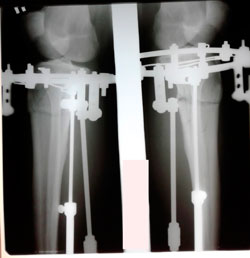

Исходник 36 лет.

Дата операции - 08.10.2020

перед крутками